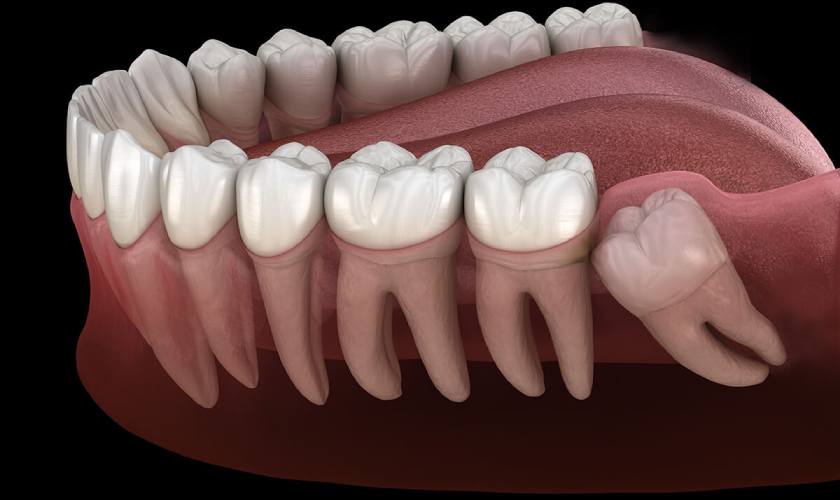

Răng khôn là chiếc răng số 8 mọc ở phía sau cùng trong cung hàm. Đây là chiếc răng mọc cuối cùng trên cung hàm nên thường không còn đủ chỗ để mọc.

Vì răng khôn thường không đủ chỗ để mọc nên chúng thường mọc nhiều góc độ khác nhau, gây đau và chèn ép răng. Các răng khác va chạm, tổn thương khiến nướu yếu đi, bị sưng đau, còn được gọi là viêm nướu răng khôn. Tình trạng này thường gặp ở nhiều người.

Răng khôn thường mọc ngầm, mọc kẹt nên dễ gây viêm nướu răng khôn